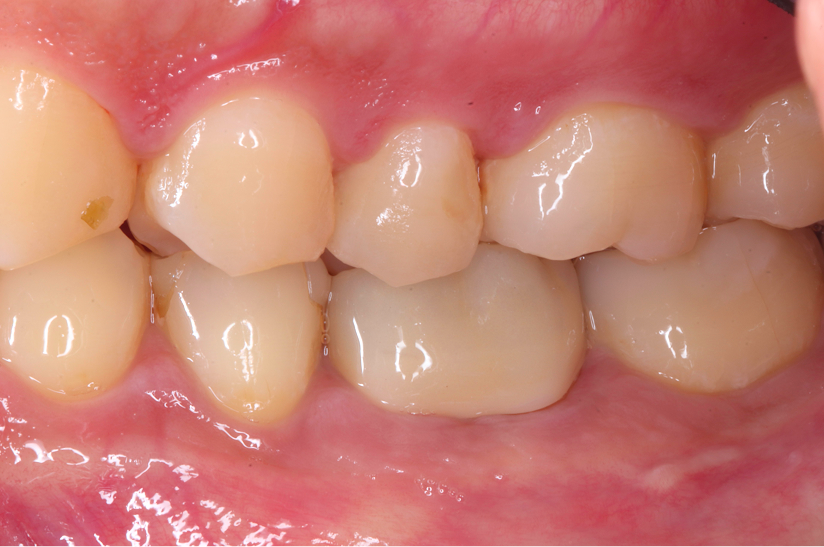

大臼歯の再根管治療を行った症例

タップで写真の拡大ができます。

Before&After(根管治療)

Before

Before&After(根管充填)

主訴

歯茎が腫れて、噛むと違和感がある

治療内容

再根管治療(大臼歯)

治療期間

1ヶ月

治療費用

165,000

治療の

リスク

処置中に歯肉縁下におよぶ重度のう蝕や破折を認めた場合、治療を中断する可能性があります。術後も症状が残る場合は追加の処置が必要になる可能性があります。